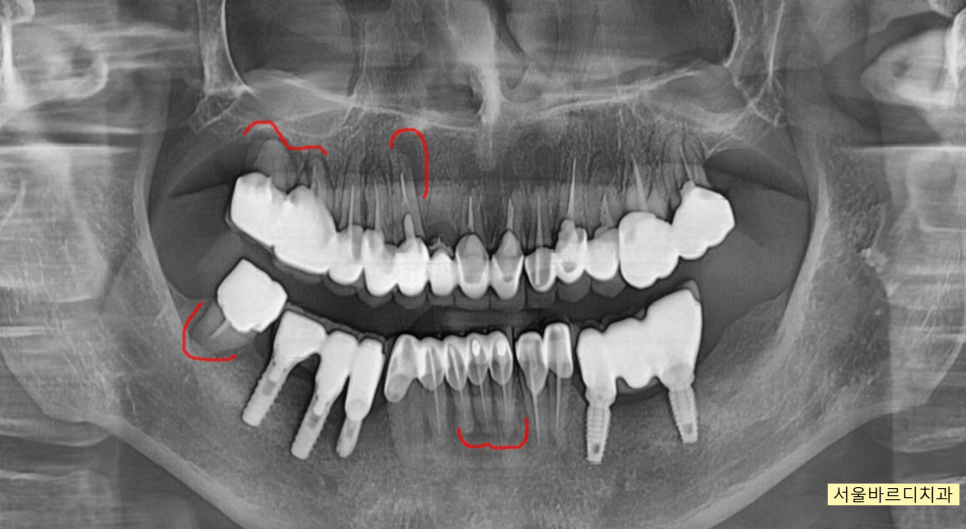

230630 녹은 경계를 확인해주세요!

x-ray 상에서도 뼈가 녹은 부분과

녹지 않은 부분이 경계져 보이는 것이 관찰되실겁니다.

녹은 부분은 까맣게 되어있고

괜찮은 부분은 하얗게 말이죠.

우선 냄새가 나는 것은 스케일링과 잇몸치료를 통하여

깨끗하게 청소하여 어느정도 해소를 하고

가장 심한 부위

염증이 있는 위아래 치아를 발치 하고

임플란트 치료하기로 말씀드렸습니다.

이 과정에서 윗니 임플란트의 경우에는

약해진 잇몸뼈를 보강해주는 "뼈이식"이 필요했습니다.

아래 치아의 경우에는

골질이 단단하여 별도의 뼈이식은 없이 진행